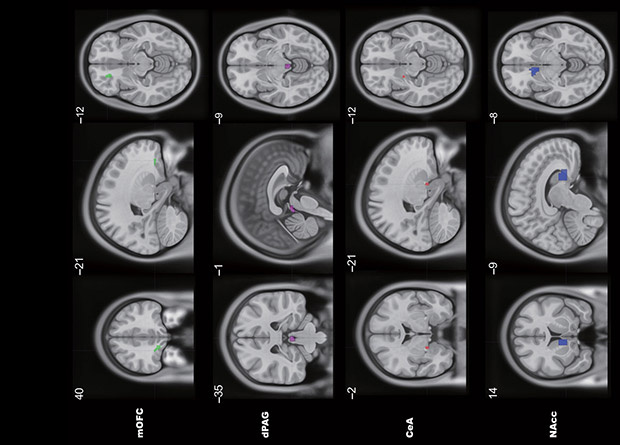

Нейронная сеть, связывающая медиальную орбитофронтальную кору с центральным серым веществом среднего мозга, участвует в формировании алкогольной зависимости у подростков двумя путями. В первом подавляется центральное серое вещество, и подросток ощущает только достоинства алкоголя, но не чувствует его побочных эффектов и не пытается остановиться, а во втором, наоборот, центральное серое вещество активируется, и подросток ощущает ситуацию как неприятную и угрожающую и, желая поскорее уйти от этого чувства, ищет избавления в алкоголе. Это ученые выяснили, изучив данные фМРТ покоя и с когнитивной нагрузкой, а также поведение почти двух тысяч подростков 14 лет, употребляющих и злоупотребляющих алкоголем, и сопоставили их с данными этих же подростков в 19 лет. Статья опубликована в журнале Science Advances.

Известно, что неконтролируемое потребление алкоголя у крыс и мышей с одной стороны связано с дефицитом экспрессии транспортера ГАМК — важнейшего тормозного нейромедиатора, в центральное ядро миндалины, из-за чего крысы предпочитают сладкому раствору алкоголь, а с другой — со снижением влияния медиальной префронтальной коры на центральное серое вещество, из-за чего грызуны перестают реагировать на негативные сигналы, в том числе не избегают алкоголь и не ощущают его побочные эффекты. Но чтобы понять, какая нейронная сеть ответственна за формирование алкогольной зависимости, необходимо не просто выделить области мозга, но и понять как эти области взаимодействуют между собой.

Тианье Цзя (Tianye Jia) из Университета Фудань и коллеги изучили поведение и данные фМРТ 1890 подростков из проекта IMAGEN в возрасте 14 лет и сопоставили их с данными этих же подростков в их 19 лет (N = 1242). Данные фМРТ были получены в состоянии покоя и во время выполнения задачи с обещанным вознаграждением (0, 2 или 10 очков: участники сначала видели стимул, обозначающий величину выигрыша, затем фокусировали внимание на белый крест, а после